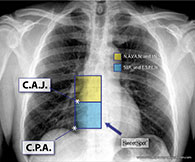

The SWEET SPOT™ is a rectangular template superimposed on a frontal CXR, whose margins and internal area are acceptable for VAD catheter tip position. This is tailored to the individual patient's chest x-ray. As such, it has no fixed length or width but does have fixed proportions with the craniocaudal length being twice the width on a frontal chest x-ray. Depending on patient anatomy, it can exceed 8 x 4 cm. The template (see Figure 01) is simply compared in size to the CXR at hand. This template is very easy to memorize and just as easy to teach.

The SWEET SPOT™ also has a fixed center point. It is centered over what I believe is the most accurate radiographic estimation of the cavo-atrial junction, i.e. on a frontal CXR, the initial outward bulge of the lower right cardiomediastinal margin due to the transition from the smaller, more tubular superior vena cava to the more capacious and rotund right atrium. It was designed to be twice as wide as the lower third of the SVC to allow for the curving course of many catheter tips as they enter the right atrium - especially with left-sided access. The SWEET SPOT™ extends from the lower third of the SVC to the most inferior extent of the right atrium - stopping at the frontal CXR's cardiophrenic angle (see Figure 01).

The SWEET SPOT™ is the best anatomically based and radiographically confirmed practical approximation of the cavo-atrial junction. It is independent of patient factors such as age, size, patient position for chest x-ray, lung volume or type of VAD. It also encompasses the various leading societal recommendations for catheter tip location (see below). As such, it allows for the necessary significant flexibility in acceptable VAD tip location based not only on patient, chest x-ray and catheter variables as just mentioned but also inserter variables such as societal affiliations, personal experience and personal convictions.

In this same trial, the vast majority of the Sherlock 3CG guided catheter tips — whose technology targets the S.A. node, were at the center of the SWEET SPOT™, i.e. the radiographic cavoatrial junction, thus confirming both chest x-ray and ECG methods of catheter tip verification. The two methods, therefore, cross-validate and have the same end point — optimal VAD tip location.